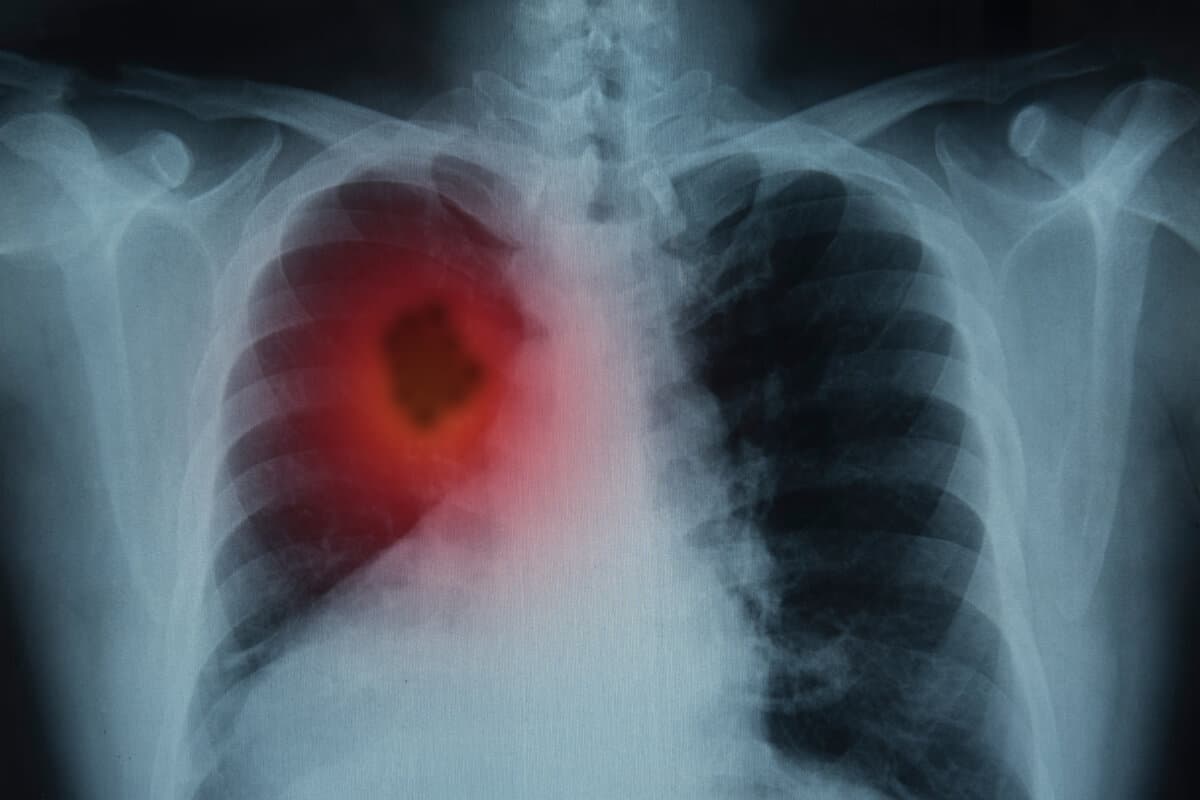

Patientinnen mit lokal rezidiviertem, inoperablem oder metastasiertem TNBC, für die eine Immuntherapie nicht infrage kommt, stehen vor einer schlechten Prognose. In der Phase-III-Studie TROPION-Breast02 verlängerte Dato-DXd als Erstlinientherapie sowohl die Gesamtüberlebenszeit als auch das progressionsfreie Überleben im Vergleich zur Chemotherapie.